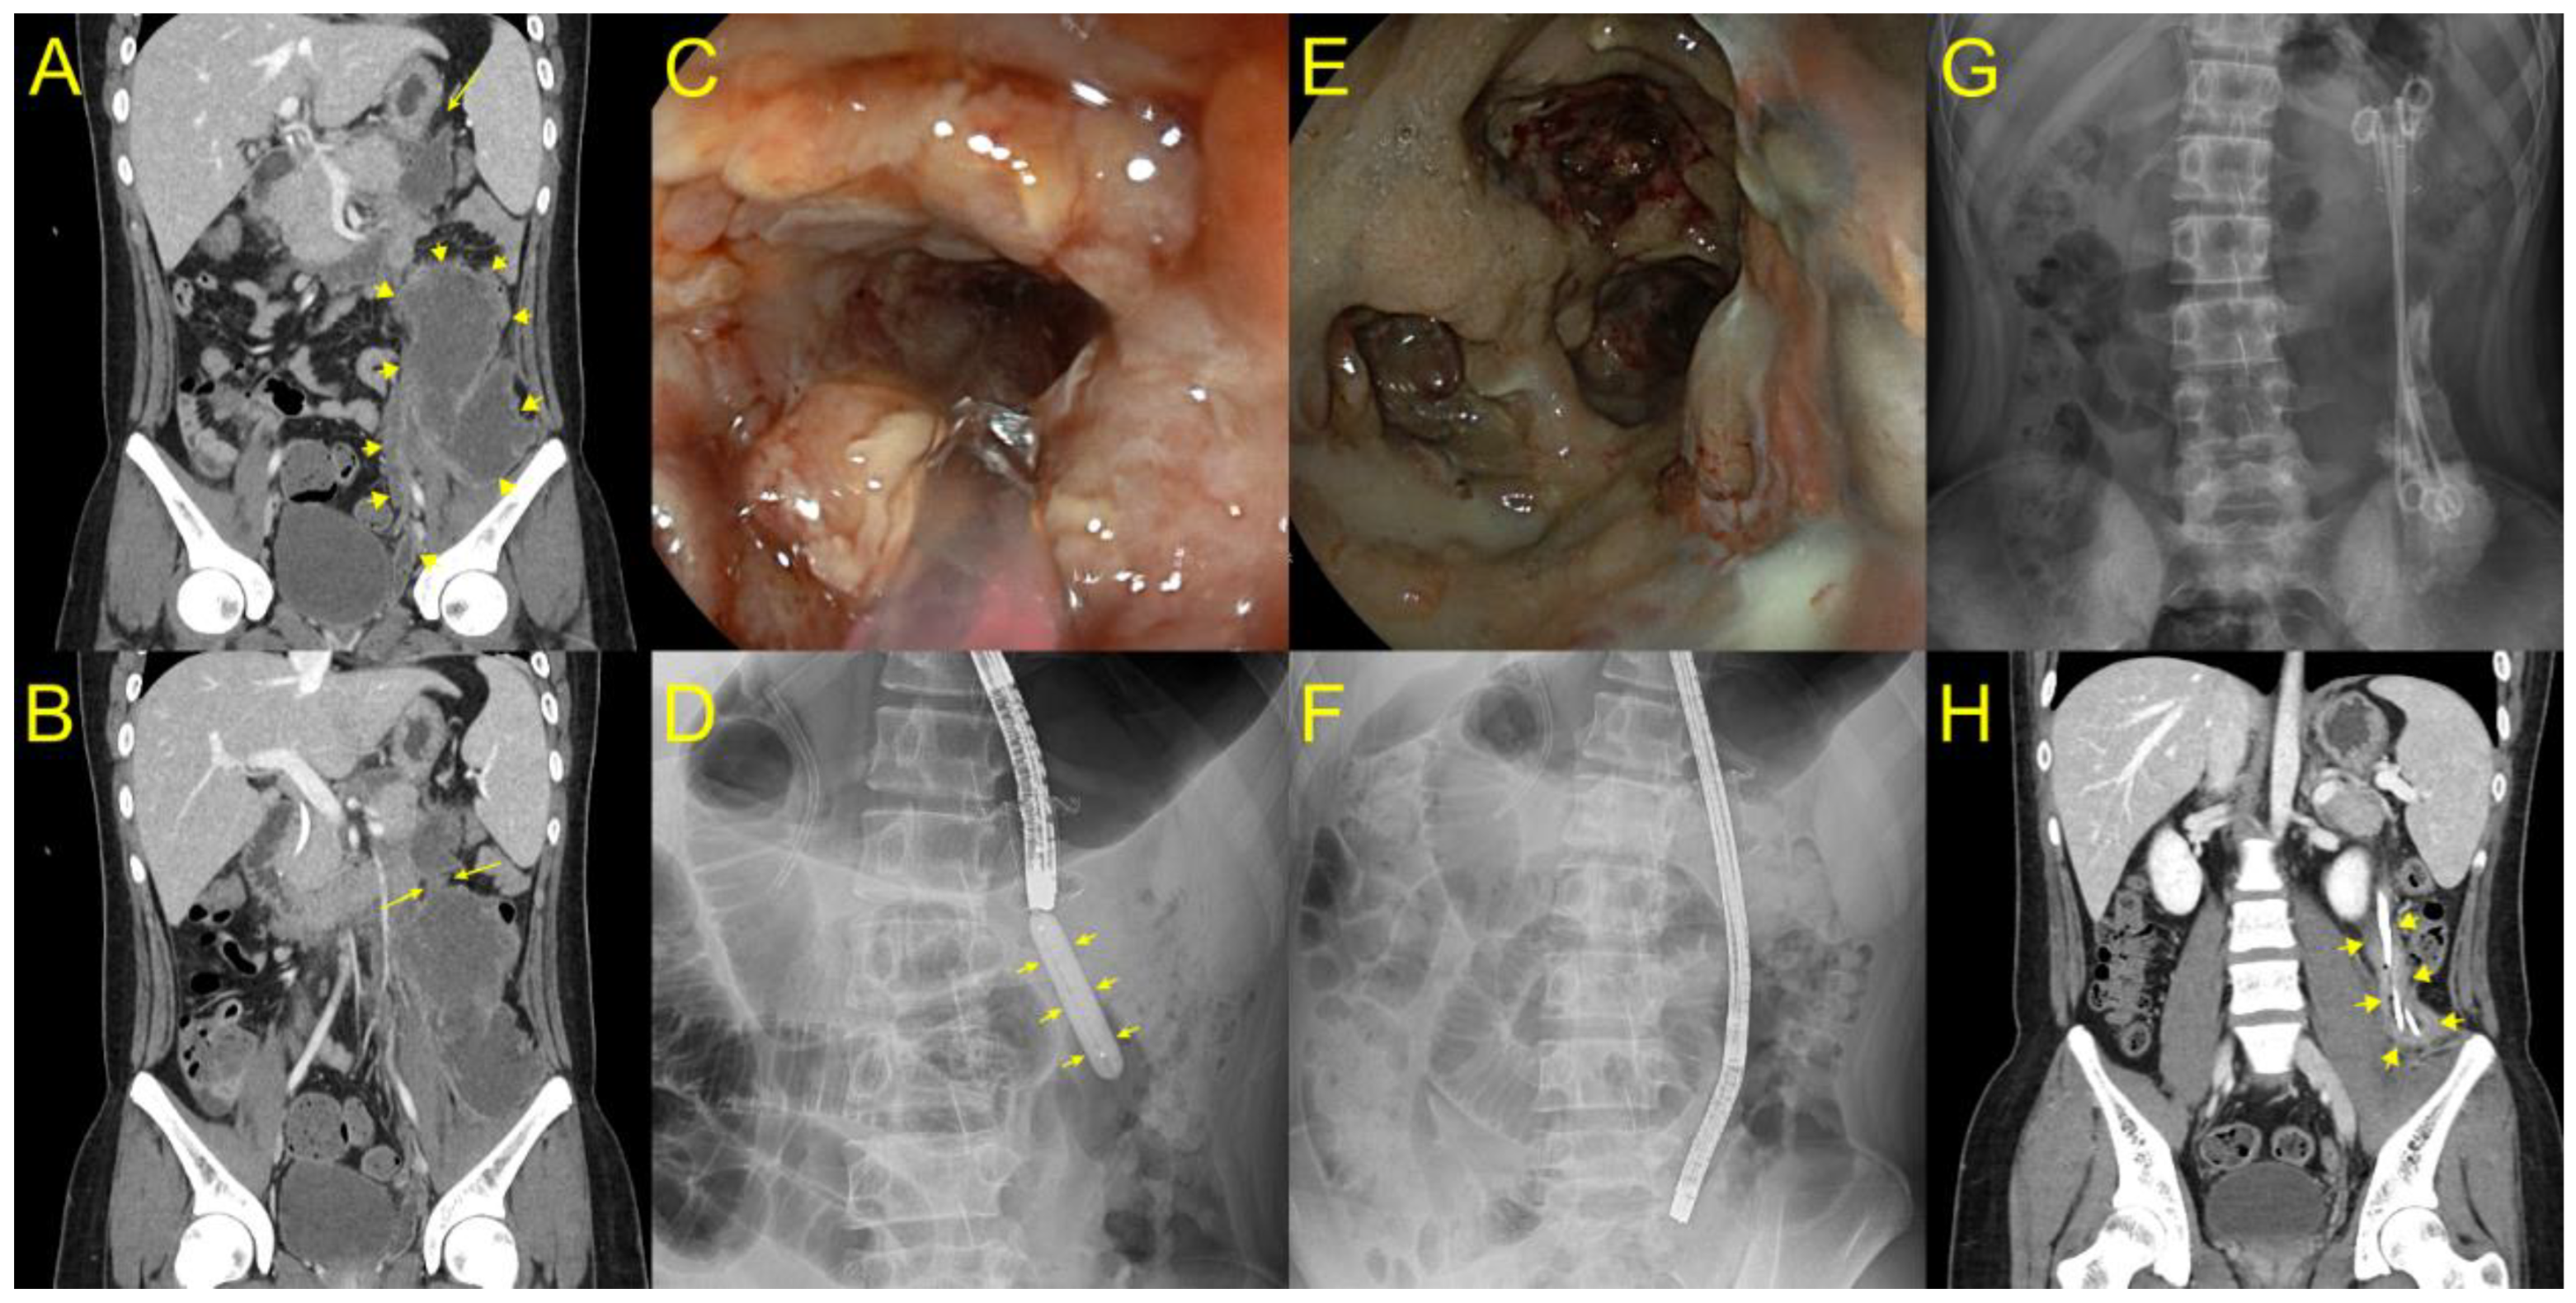

Figure 2. Placement of long plastic stents to the deep portion of walled off necrosis (WON) after direct endoscopic necrosectomy (DEN) for endoscopic treatment of laterally extended WON (yellow arrow) (A). (B) Computed tomography showing a huge WON extended to the left pelvic cavity communicating to a small portion of the necrotic cavity concatenated with the stomach through the narrow neck (yellow arrow) portion. (C) A gastroscope was inserted into the proximal portion of WON through a lumen-apposing metal stent (LAMS), and we found a luminal stricture of the neck portion of WON. (D) Balloon dilatation (yellow arrow) was performed for deep insertion of an endoscope to the laterally extended WON. (E,F) The cavity was lavaged with normal saline, and necrotic debris was progressively removed with snare and grasping forceps. (G) After DEN, three plastic stents with double pigtail configuration were fixed in place through the LAMS to the deep portion of WON until the next session of DEN. (H) After 16 DEN sessions, where the long plastic stents remained in the deep portion of WON, the patient recovered with complete WON resolution (yellow arrow).